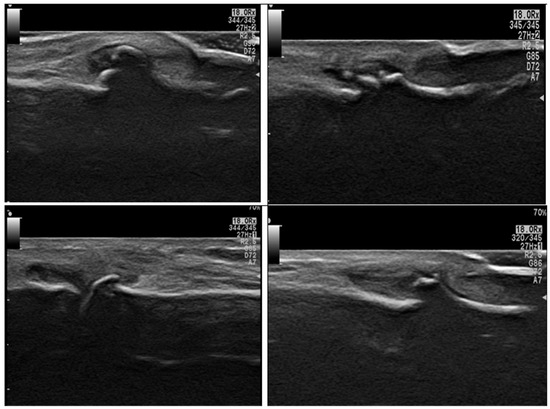

2.5. Musculoskeletal Ultrasound Examination

- Bruyn, G.A.; Iagnocco, A.; Naredo, E.; Balint, P.V.; Gutierrez, M.; Hammer, H.B.; Collado, P.; Filippou, G.; Schmidt, W.A.; Jousse-Joulin, S.; et al. OMERACT Definitions for Ultrasonographic Pathologies and Elementary Lesions of Rheumatic Disorders 15 Years On. J. Rheumatol. 2019, 46, 1388–1393. [Google Scholar] [CrossRef]

- Di Matteo, A.; Mankia, K.; Azukizawa, M.; Wakefield, R.J. The role of musculoskeletal ultrasound in the rheumatoid arthritis continuum. Curr. Rheumatol. Rep. 2020, 22, 41. [Google Scholar] [CrossRef]